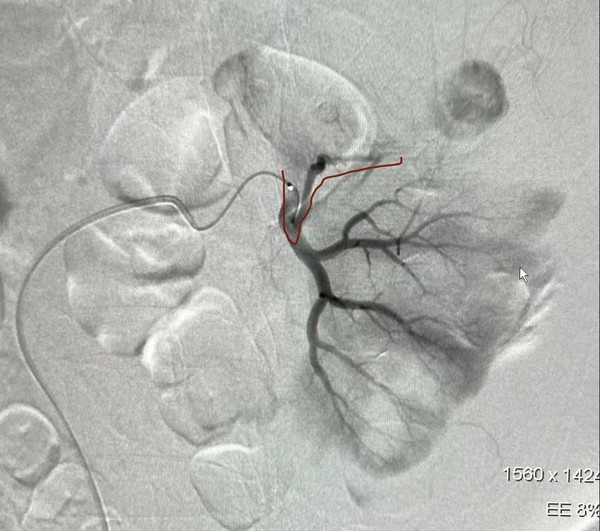

患者女,69岁,系高难度肾错构瘤患者,因肿瘤较大,外科手术难以剥离,经与患者及家属沟通后决定急诊实施介入治疗。一月后,为了巩固疗效,预防肿瘤生长后再破裂、减少复发的风险,3月2日,患者在我院继续针对全部肿瘤血管栓塞治疗。行DSA造影见肿瘤血供丰富,上次栓塞后的左肾上前段动脉对肿瘤供血明显,依次逐一栓塞其它血管后,采用多种导管模式仍无法超选该血管,术中血压一过性上升至210/120mmHg,请心内科会诊,采用冠脉球囊临时阻断下前段动脉远端正常血供后,注射明胶海绵颗粒顺利全部进入该血管达到完整栓塞目的。